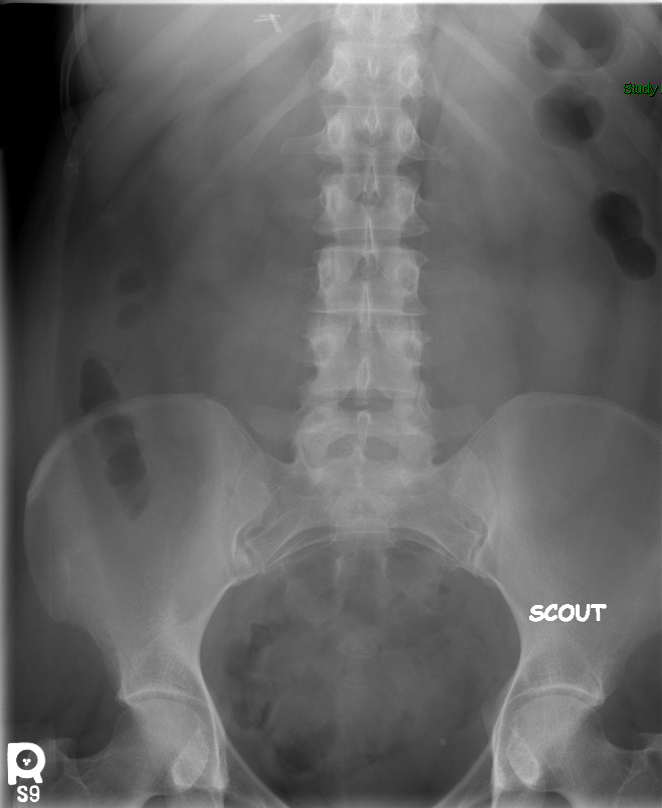

- The technologist will obtain a scout image. Assess the image for any possible contraindications such as pneumoperitoneum, evidence of ileus or obstruction, or residual contrast material

(key image 1).

- The technologist will obtain a scout image

- Review the scout image, looking for any contraindications to performing the procedure (pneumoperitoneum, pneumatosis, etc.).